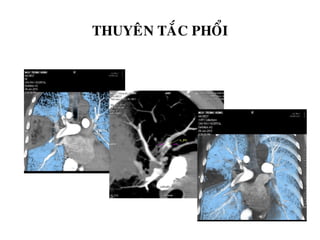

THUYEÂN TAÉC PHOÅI

Hình CT

-Khuyeát trong loøng maïch

do cuïc maùu ñoâng

-Vuøng taêêng ñaäm ñoä, hình

cheâm, neàn döïa vaøo maøng

phoåi (nhoài maùu phoåi)

-Roái loïan thoâng khí

Thuyeân taéc ñoäng maïch phoåi: hình

khuyeát thuoác (maùu ñoâng) ôû ngoaïi bieân

cuûa ñoäng maïch phoåi (T)

Thuyeân taéc ñoäng maïch phoåi keøm nhoài maùu phoåi: vuøng nhoài maùu

hình tam giaùc, vôùi ñaùy roäng ôû phiaù ngoaïi bieân

- Tắc động mạch phổi (Pulmonary embolism – PE) là bệnh lý tim mạch cấp tính

thường gặp.

- Bệnh đứng hàng thứ 3 sau nhồi máu cơ tim và tai biến mạch máu não. (the third most

common acute cardiovascular disease after myocardial infarction

and stroke).

- Hàng ngàn case tử vong mỗi năm do không chẩn đoán được bệnh.